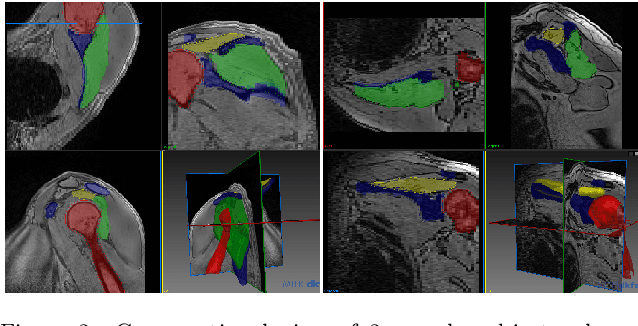

Abstract:Segmentation of anatomical structures is a fundamental image analysis task for many applications in the medical field. Deep learning methods have been shown to perform well, but for this purpose large numbers of manual annotations are needed in the first place, which necessitate prohibitive levels of resources that are often unavailable. In an active learning framework of selecting informed samples for manual labeling, expert clinician time for manual annotation can be optimally utilized, enabling the establishment of large labeled datasets for machine learning. In this paper, we propose a novel method that combines representativeness with uncertainty in order to estimate ideal samples to be annotated, iteratively from a given dataset. Our novel representativeness metric is based on Bayesian sampling, by using information-maximizing autoencoders. We conduct experiments on a shoulder magnetic resonance imaging (MRI) dataset for the segmentation of four musculoskeletal tissue classes. Quantitative results show that the annotation of representative samples selected by our proposed querying method yields an improved segmentation performance at each active learning iteration, compared to a baseline method that also employs uncertainty and representativeness metrics. For instance, with only 10% of the dataset annotated, our method reaches within 5% of Dice score expected from the upper bound scenario of all the dataset given as annotated (an impractical scenario due to resource constraints), and this gap drops down to a mere 2% when less than a fifth of the dataset samples are annotated. Such active learning approach to selecting samples to annotate enables an optimal use of the expert clinician time, being often the bottleneck in realizing machine learning solutions in medicine.

Abstract:Segmentation is essential for medical image analysis tasks such as intervention planning, therapy guidance, diagnosis, treatment decisions. Deep learning is becoming increasingly prominent for segmentation, where the lack of annotations, however, often becomes the main limitation. Due to privacy concerns and ethical considerations, most medical datasets are created, curated, and allow access only locally. Furthermore, current deep learning methods are often suboptimal in translating anatomical knowledge between different medical imaging modalities. Active learning can be used to select an informed set of image samples to request for manual annotation, in order to best utilize the limited annotation time of clinical experts for optimal outcomes, which we focus on in this work. Our contributions herein are two fold: (1) we enforce domain-representativeness of selected samples using a proposed penalization scheme to maximize information at the network abstraction layer, and (2) we propose a Borda-count based sample querying scheme for selecting samples for segmentation. Comparative experiments with baseline approaches show that the samples queried with our proposed method, where both above contributions are combined, result in significantly improved segmentation performance for this active learning task.